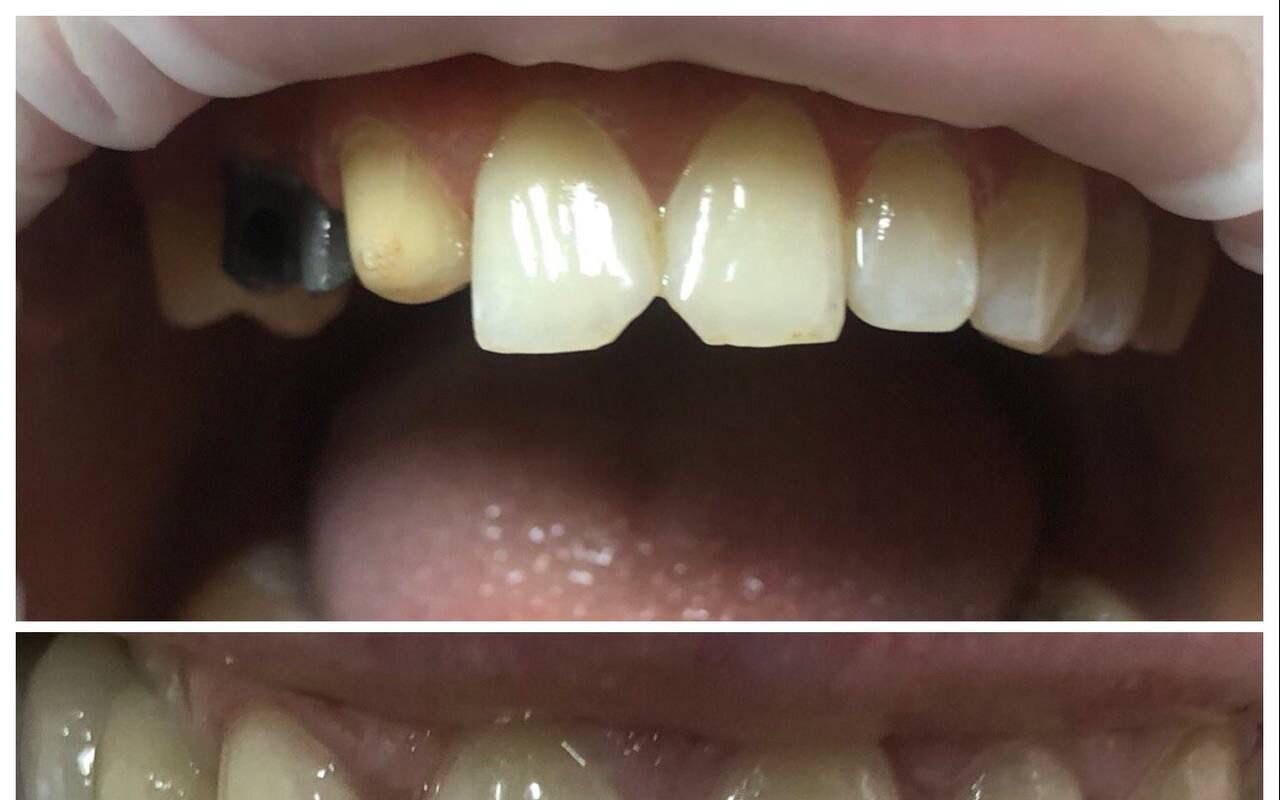

Стоматолог-ортопед, хирург, имплантолог

Синанян Хачатур Георгиевич является стоматологом-ортопедом, а также работает в сфере имплантологии и стоматологической хирургии. Хачатур Синанян в том числе делает пластику десны, уздечки губ и языка и тканей полости рта, устанавливает условно-съемные протезы, металлокерамические и безметалловые протезы, штифты, вкладки и виниры, а также выполняет несъемное и съемное протезирование зубов, микропротезирование зубов, шинирование зубов и синус-лифтинг.... Показать еще

Фото работ врача Хачатура Георгиевича Синаняна